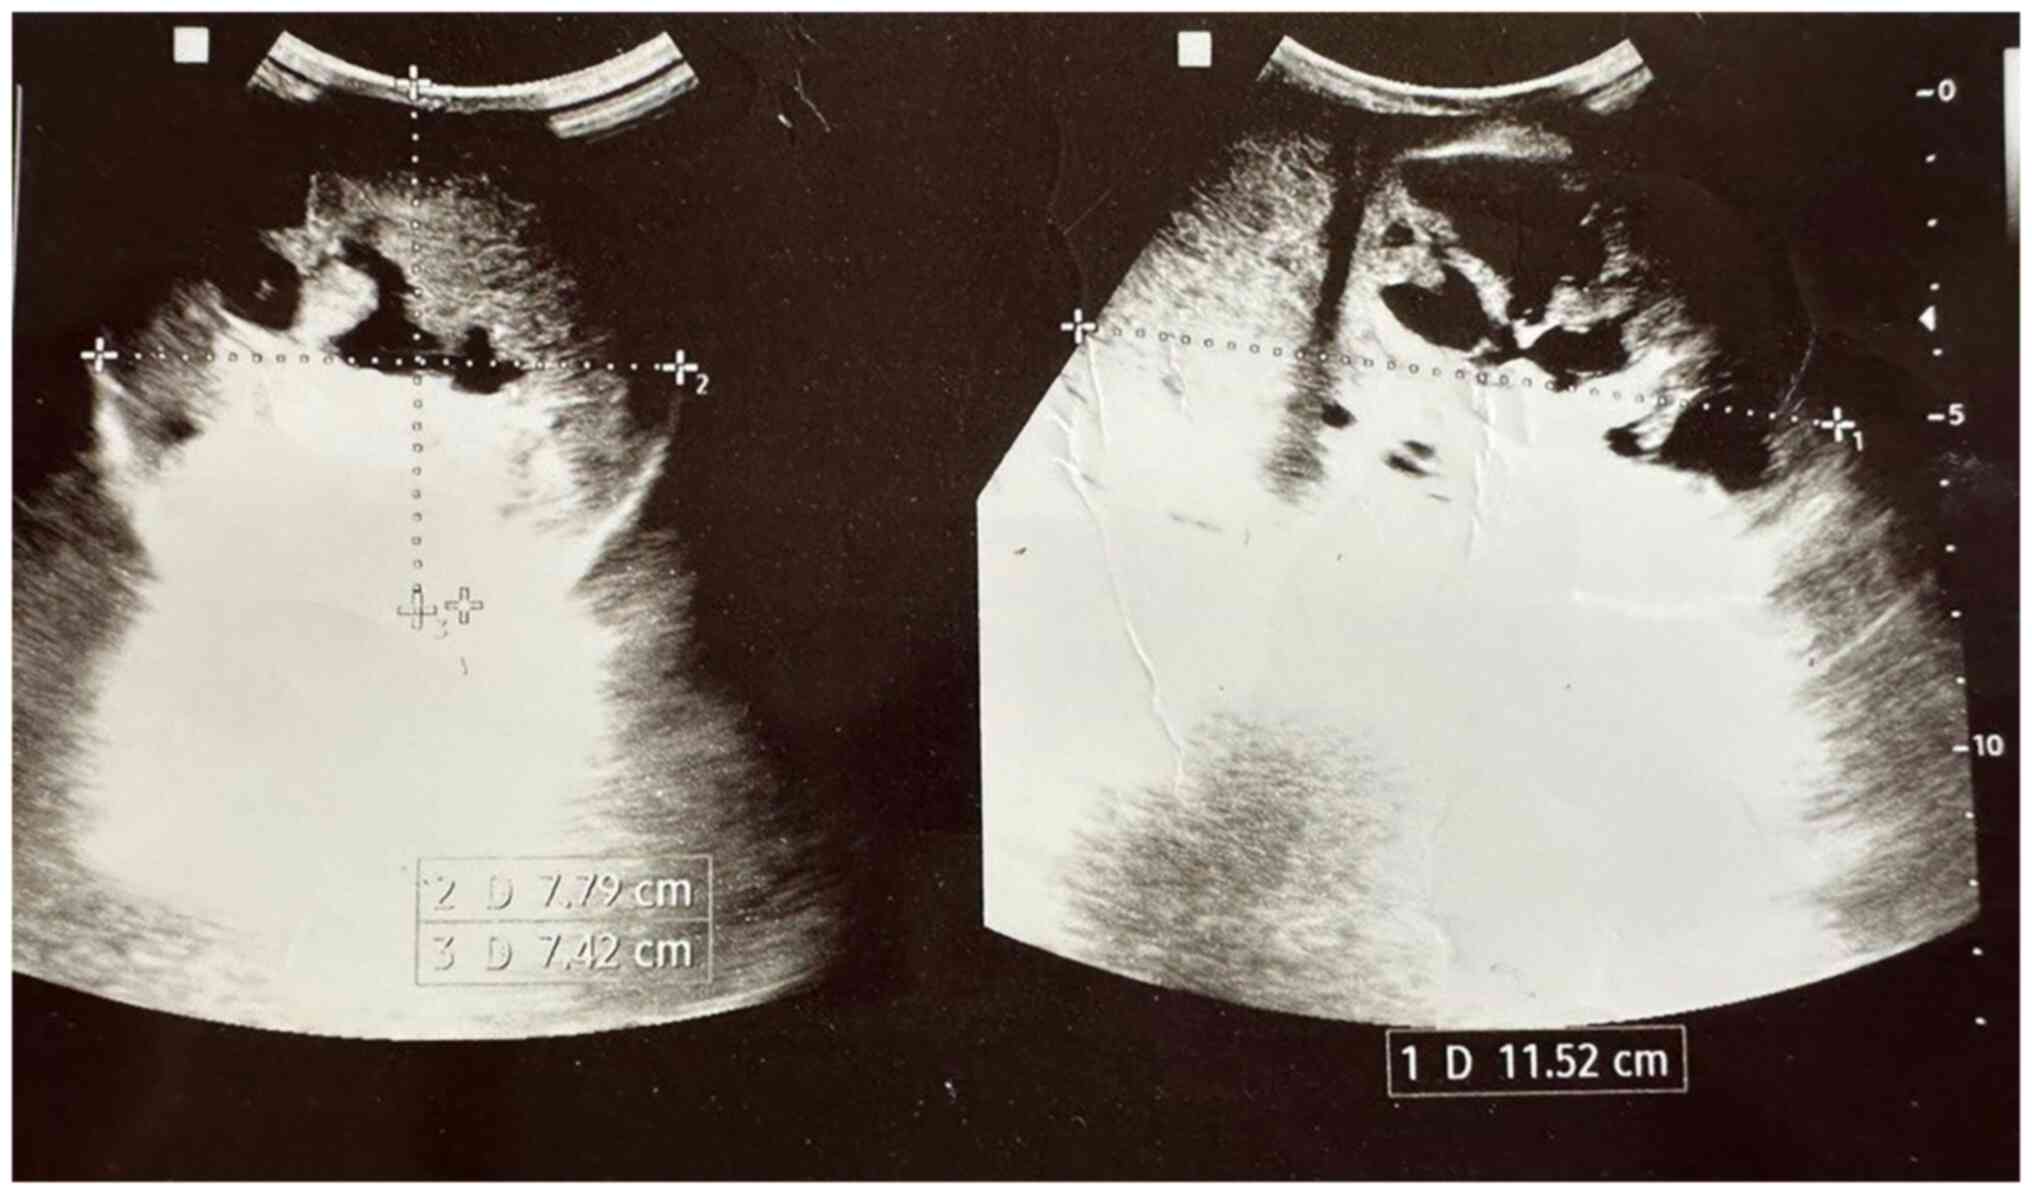

The levels of tumor markers, including alpha-fetoprotein (AFP; 1.81 ng/ml; normal range, 0-40 ng/ml) and human chorionic gonadotropin (hCG; 0.448 µIU/ml; normal range, <3 µIU/ml) were within normal limits, while those of lactate dehydrogenase were elevated to 400.3 U/l (normal range, 135-225 U/l). Scrotal ultrasound (US) imaging revealed a complex heterogeneous mass almost replacing the right testis and measuring 11x8x7 cm (Fig. 1), while the left testis appeared normal. No para-aortic lymph nodes were detected on an abdominal US scan.

Figure 1

Two orthogonal planes of ultrasound images illustrating a large, well-circumscribed, solid mass measuring 11x7x8 cm, completely replacing the right testicle. The lesion exhibited multifocal cystic degeneration resulting in posterior acoustic enhancement.

In the case presented herein, scrotal US imaging revealed a complex heterogeneous mass almost replacing the right testis, confirming the presence of a sizable tumor. The absence of para-aortic lymph nodes on abdominal ultrasound scan suggested localized disease without metastasis (13,14). Another study on managing 21 cases reported no metastasis (8). Although, other scholars have reported 14 cases of metastasis out of 146 cases, and ScTs with other histological variants such as sarcoma and anaplastic tumors tend to metastasize more than the pure ScTs (5,8). Despite the absence of trials regarding the management of ScTs, however, orchiectomy remains the standard treatment option based on the reports and clinical series (5). Testis sparing surgery is not recommended due to the difficulty of differentiating ScTs from pure seminoma, in some cases even in frozen section analysis (5). The case in the present study underwent radical orchiectomy, which allows for accurate staging and histopathological examination of the excised specimen (5). The differential diagnoses of ScTs in histopathological or immunohistochemistry can be classical seminoma, embryonal cancer and non-Hodgkin lymphoma. Hence, it is recommended for pathologists to be firmly aware of the distinctive features of each disease (8). In the case in the present study, histopathological and immunohistochemical analyses confirmed the diagnosis of a spermatocytic tumor. Post-operatively, the patient had an uneventful recovery. Metastatic workup, including chest and abdominal CT scans, revealed no evidence of metastasis. Regular follow-up appointments were scheduled to monitor the patient's condition and detect any potential recurrence or metastasis. Long-term surveillance is crucial due to the risk of late recurrence, even though these tumors tend to exhibit a slow and indolent course (15,16).